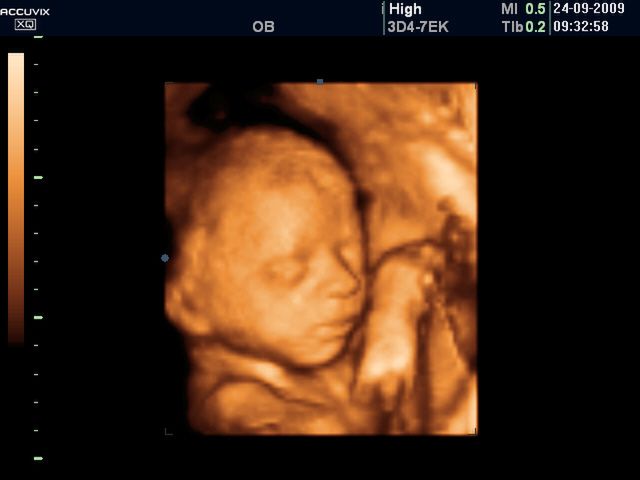

/ 5Płód w 26 tygodniu ciąży - twarz dziecka

W 26 tygodniu oczy dziecka otwierają się